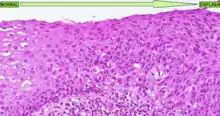

A displasia é essencialmente uma desespecialização do tecido, ele fica mais imaturo e afasta-se do aspeto normal. É frequente que no microscópio seja possível observar em uma displasia:

- Pleomorfismo celular (células com tamanhos e formas diferentes entre si)

- Atipia nuclear (células com núcleo irregular) com hipercromatasia (núcleo mais escuro que indica que o tecido está com alta atividade proliferativa)

- Perda da arquitetura normal do tecido (p. ex.: glandulas irregulares e dismórficas)

- Pseudoestratificação ou estratificação completa de epitélios simples (em monocamada)

- usualmente com perda de polaridade celular, na qual os núcleos podem estar tanto orientados perto do pólo basal como do apical ou ao centro)

- Aumento da relação núcleo/citoplasma (núcleo maior e ou citoplasma mais pequeno)

- Presença de nucléolo quando não é normal naquele tecido tê-lo visível (é um sinal forte de indiferenciação celular também)

- Células binucleadas (é mais raro acontecer, mas deve-se a mitoses muito frequentes aumentando a hipótese de haverem erros na replicação celular)

A displasia pode ter outras caraterísticas específicas para um tecido ou para outro, mas estas são as caraterísticas principais mais comuns à maioria dos tecidos.